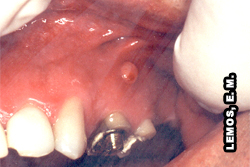

Edema localizado. Dente responsável 21 - abscesso apical agudo |

Fístula vestibular anterior superior direita. Dente responsável 11, abscesso apical crônico |

Edema localizado. Dente responsável 14 - abscesso apical agudo |